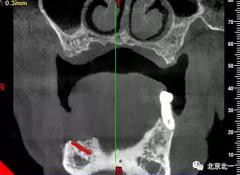

圖一至圖六明顯看出右側(cè)頦孔位于牙槽嵴頂。很清晰看出頦孔區(qū)的U型形狀。

圖七:采用A04技術(shù),拔除下頜余留牙,修整骨平面。在頦孔前方傾斜植入兩枚植體,避開頦孔。減少懸臂。前牙區(qū)植入兩枚直的植體。完成即刻修復(fù)。一日得牙,缺牙后多少年來都沒有吃過蘋果的滋味,到種植牙時(shí)代,想吃什么就吃什么, 我的健康我做主。